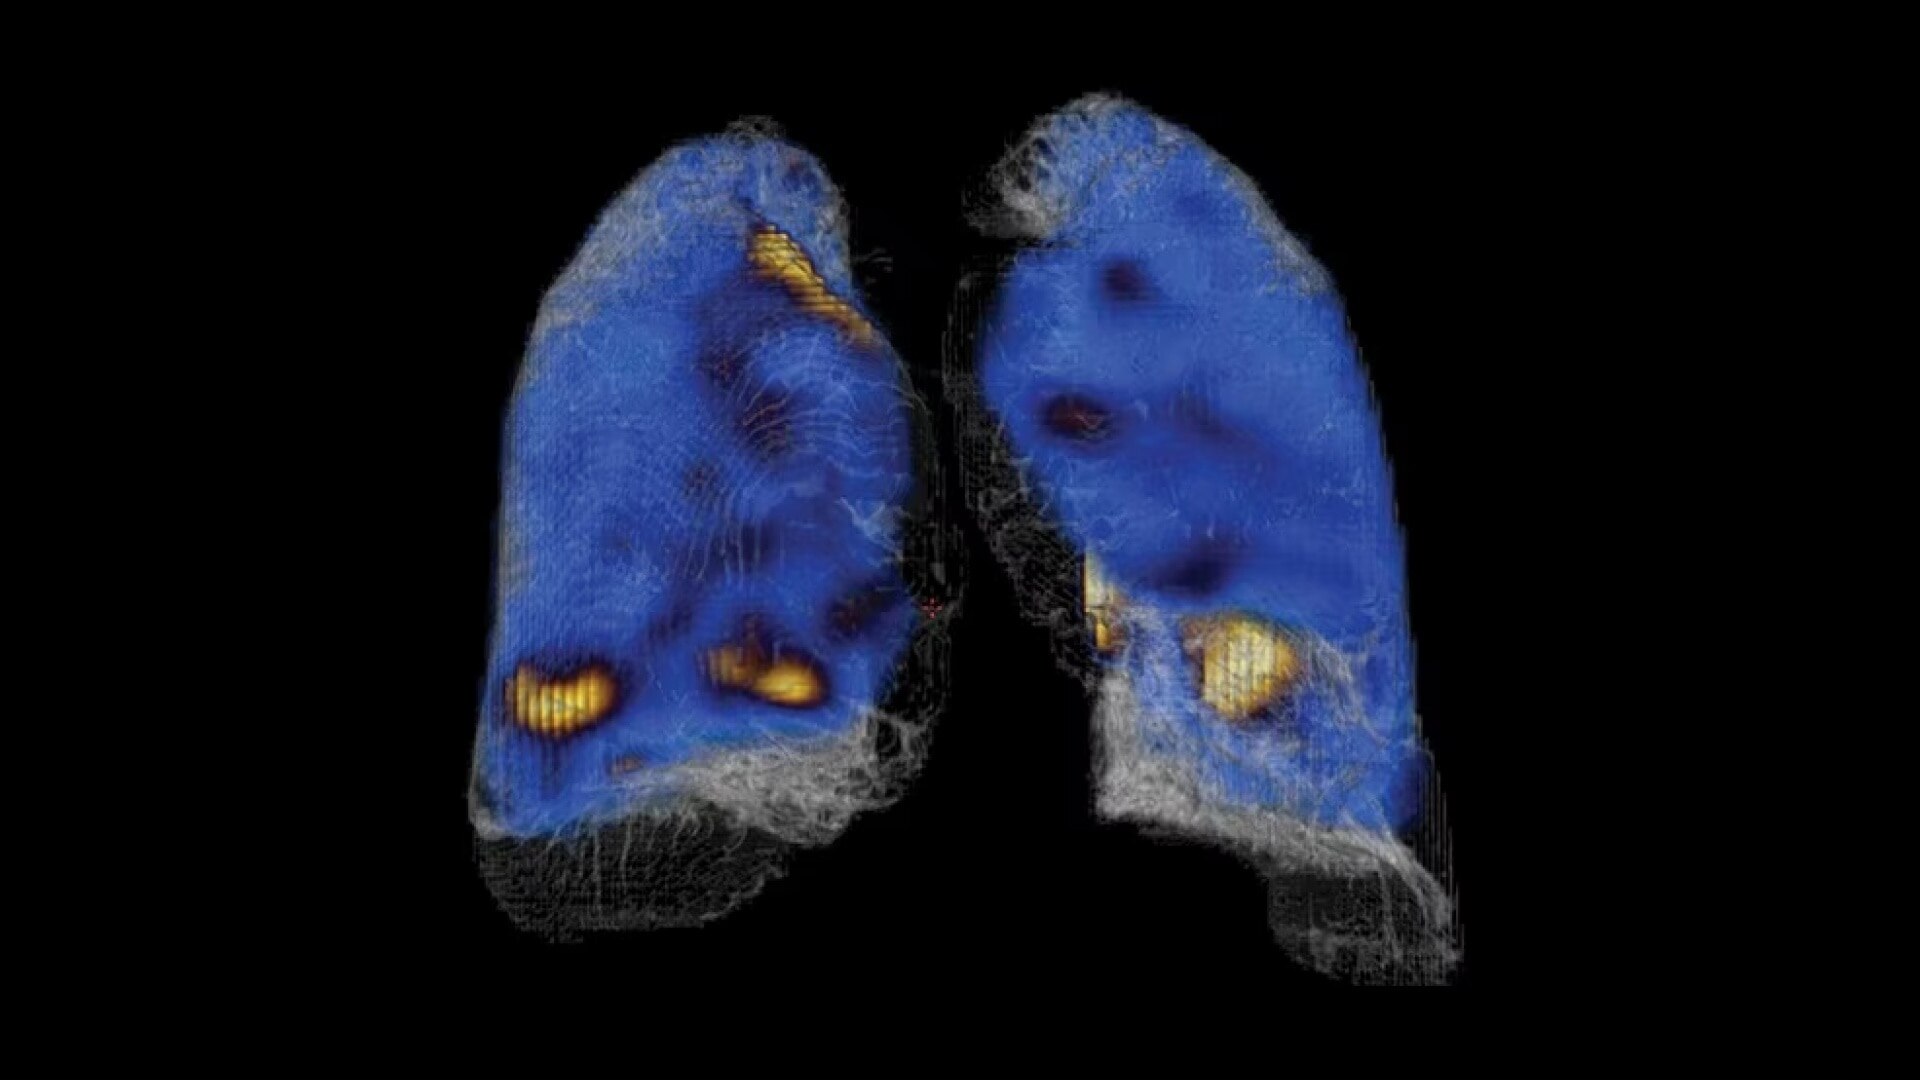

Stay on top of the latest trends in imaging

NM/CT 850 allows you to provide referring physicians with a wide range of valuable services, including emerging trends in surgical and therapy planning. Services like the ability to calculate a lung cancer patient’s current lung capacity and accurately estimate what their post-operative lung capacity will be. And the ability to provide surgeons with a roadmap to find and remove affected nodes during sentinel node dissections. In addition, Revolution ACTs has the dose reduction technology referring physicians expect with every SPECT/CT exam.